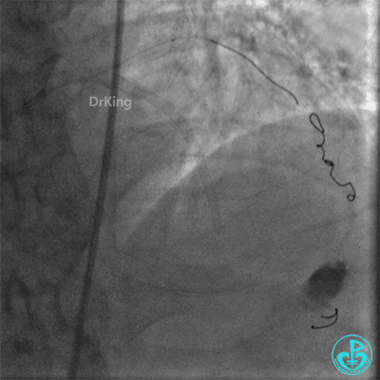

钝缘支分支远端破口完全闭塞。

封堵后观察半小时,患者血压逐步回升,维持在(100~110)/(50~60)mmHg,心率下降至90次/分。

出院随访

出院后1年复查造影,前降支支架通畅,血流3级。患者无明显胸闷、胸痛、喘憋等症状,日常活动不受限制。